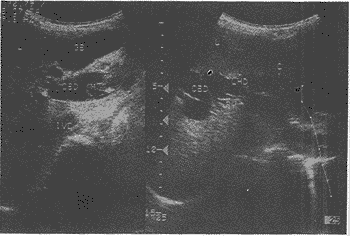

患者,女,46岁。因阴道不规则流血1年,伴有恶臭血性分泌物2月来诊。B超检查示: 子宫前位,宫体9.0cm×7.1cm×6.8cm,肌层回声均匀;宫颈增大,宫颈管腔内示7.5cm ×4.5cm×4.6cm高回声团,边界清,较规则,内部回声不均匀,可见多处不规则小低回声 ,并示一长4.5cm,厚2.4cm高回声蒂连于宫腔内(图1);阴道内示片状无回声,透声不佳。 B超诊断:宫腔内息肉脱入宫颈管内;阴道积血。妇科检查:清理阴道内积血后发现宫颈口 扩张,内见一灰红色团块,较圆钝,质地硬,可推动,考虑为子宫粘膜下肌瘤脱入宫颈管内 。两天后患妇阴道内脱出一约7cm×4cm×5cm灰红色肉团,质地硬。病理示:子宫内膜息肉 。

图1 子宫(UT),息肉脱入宫颈管(CX)内